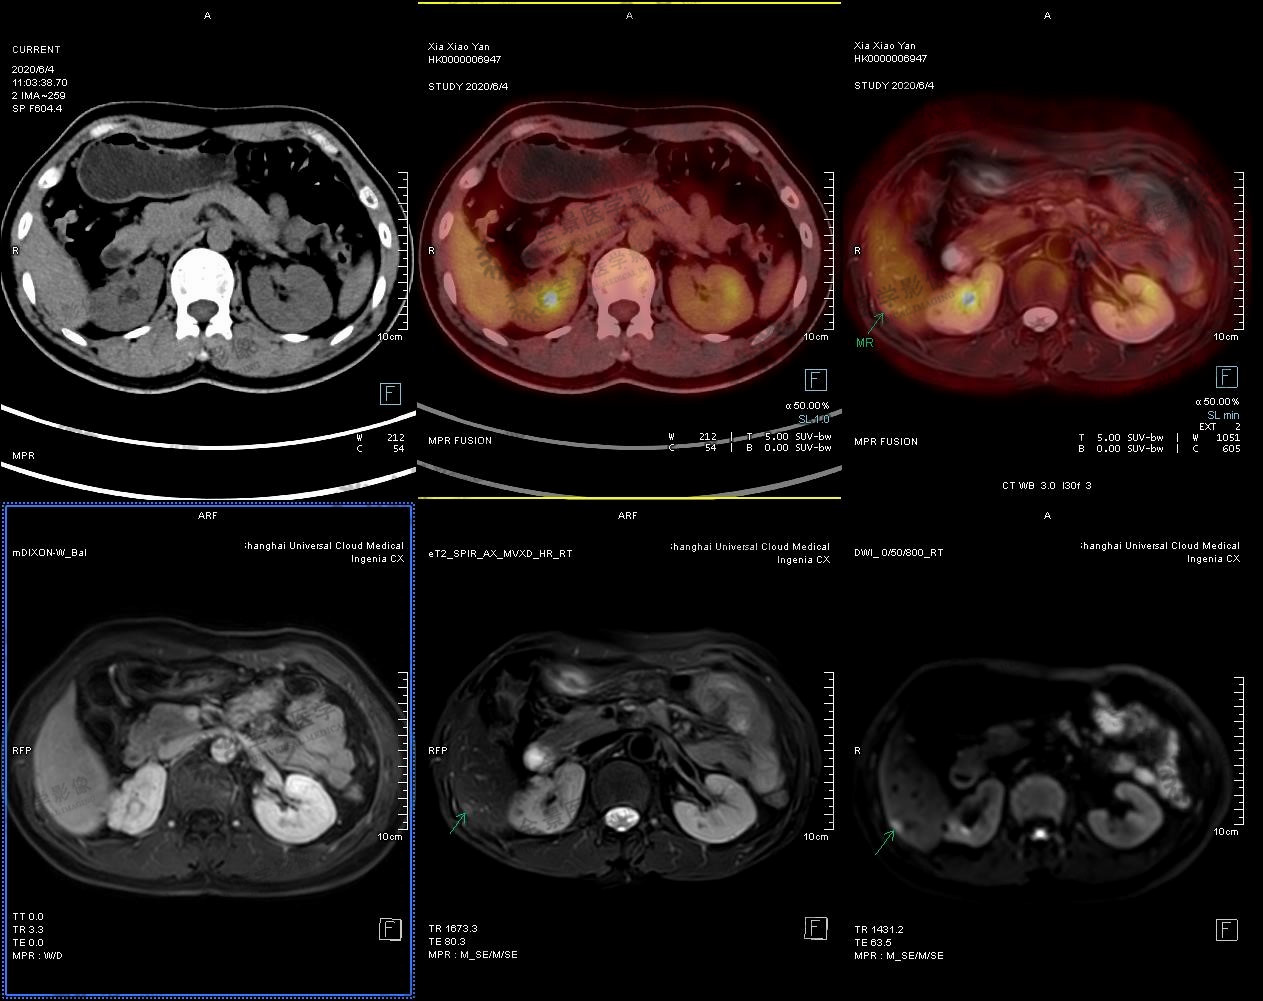

实例一

中年女性 外院体检发现肝脏小结节,乙肝病史不详。无明显不适症状。2020.5 于本中心行腹部MRI示:肝右后叶下段包膜下小结节,考虑小肝癌可能。

肝右后叶下段包膜下小结节,考虑小肝癌